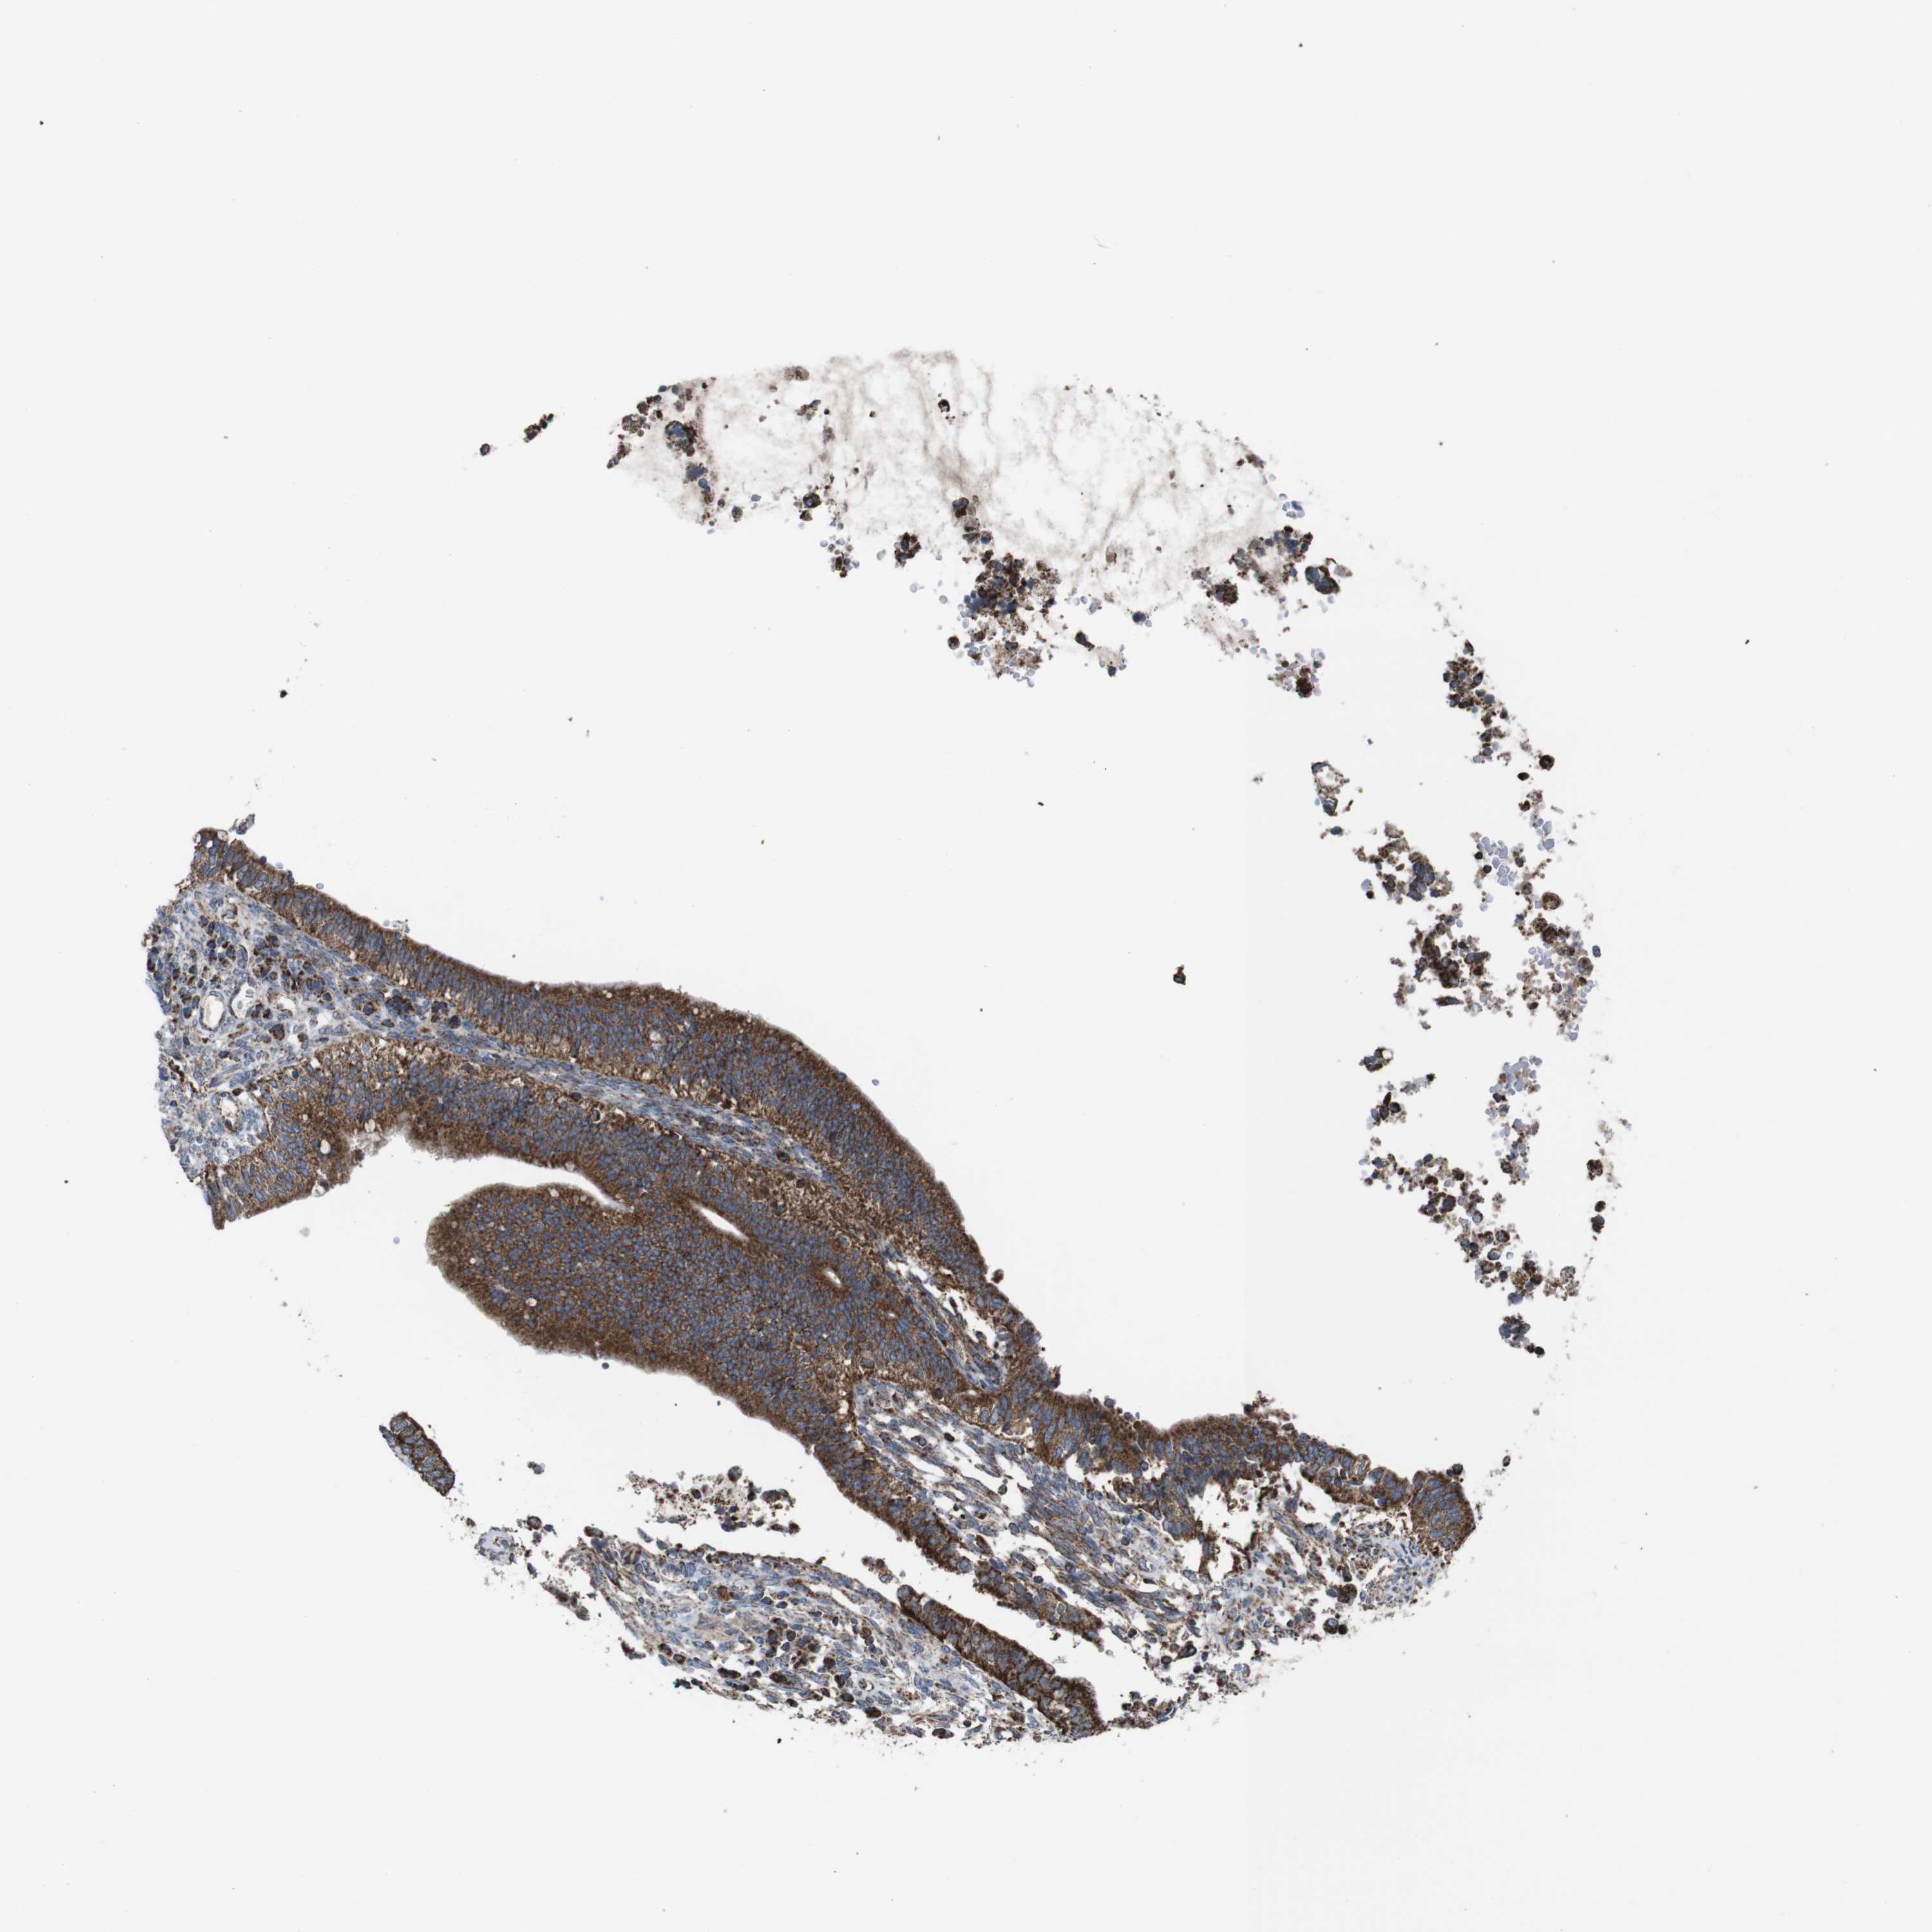

CERVICAL CANCER - Protein expressioni

A mouse-over function shows sample information and annotation data. Click on an image to view it in a full screen mode. Samples can be filtered based on level of antibody staining by selecting one or several of the following categories: high, medium, low and not detected. The assay and annotation is described here.

Note that samples used for immunohistochemistry by the Human Protein Atlas do not correspond to samples in the TCGA dataset.

Antibody stainingi

Antibody staining in the annotated cell types in the current human tissue is reported as not detected, low, medium, or high, based on conventional immunohistochemistry profiling in selected tissues. This score is based on the combination of the staining intensity and fraction of stained cells.

Each image is clickable and will lead to virtual microscopy that enables deeper exploration of all samples and also displays staining intensity scores, fraction scores and subcellular localization as well as patient and tissue information for each sample.

Antibody HPA007043

Antibody HPA007044

Antibody CAB010052

Squamous cell carcinoma, NOS

Adenocarcinoma, NOS